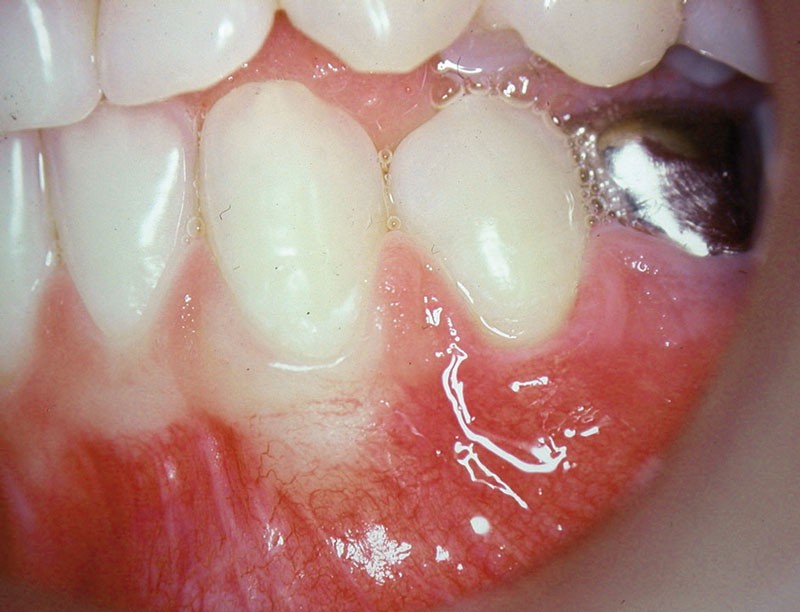

Cas clinique 2

Dans ce deuxième cas, la canine mandibulaire présente également une absence de gencive attachée, associée ici à une récession gingivale (fig. 3).

Une greffe épithélio-conjonctive est réalisée (fig. 4).

Positionnée plus coronairement que la précédente (fig. 5), elle permettra de recouvrir la récession et de recréer un lambeau de gencive attachée (fig. 6).